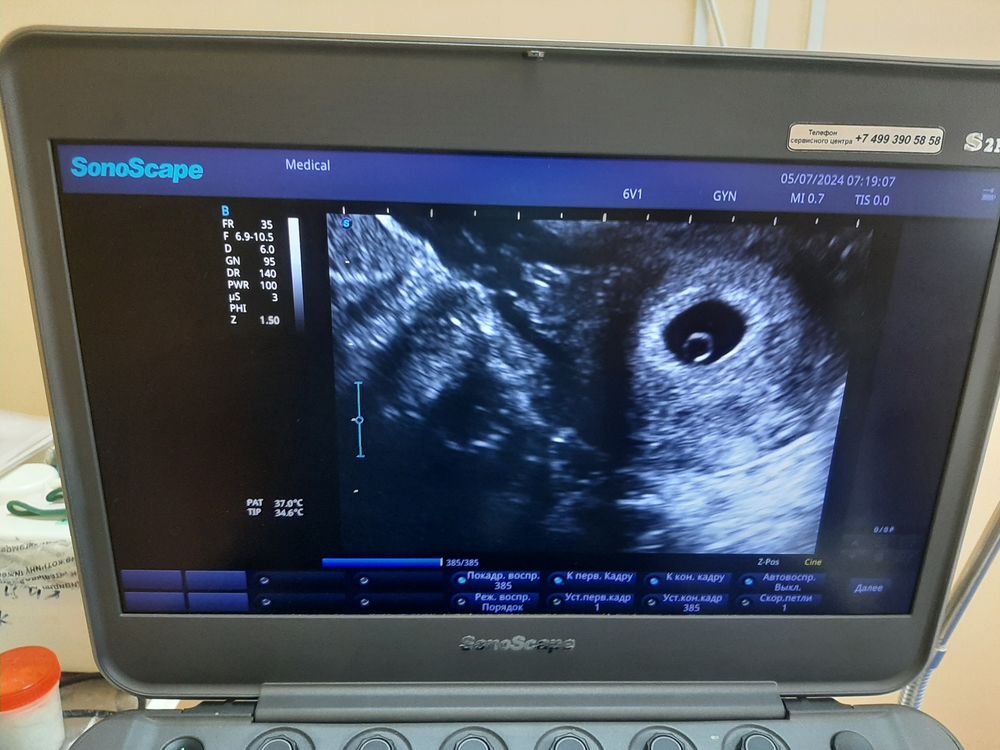

Беременность 6 недель

Плодное яйцо пустое, тут можно подождать еще пару дней и сходить на узи искать ЖМ. У меня при таком размере ПЯ, ЖМ был 3 мм. Хоть бы у Вас не анэмбриония

Что-то странное написано.. где там плод, я вижу пустое пя.. То что желточного мешка нет это нехорошо. Срочно переделывать смысла нет, подождите неделю и сходите к другому врачу, тут уже либо всё, что нужно появится, либо анэмбриония

Olga, жм появился и матка приняла нормальную форму,эмбриончика пока что не видно,жёлтое тело тоже есть Изображение

Karmilla, жм появился и матка приняла нормальную форму,эмбриончика пока что не видно,жёлтое тело тоже есть Изображение